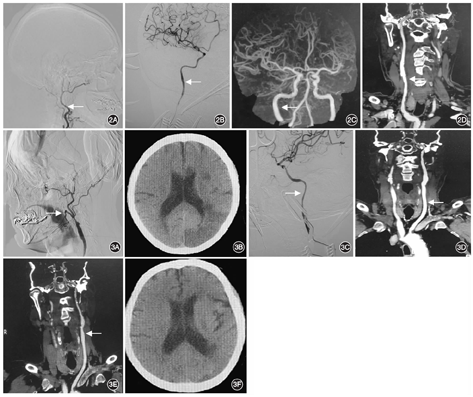

例2男,68岁,主因左侧肢体无力14 d入院。既往有高血压、脑梗死病史。体格检查:神志清楚,言语流利,双侧瞳孔等大,直径约2.5 mm,对光反射灵敏,四肢肌力、肌张力正常。治疗方法同例1。患者未发生围手术期卒中,术后5~7 d复查头颈上胸段CTA可见颈动脉斑块切除,血管再通(图2)。术后3~6个月随访,患者的症状消失,未再出现缺血性脑血管病相关症状,未复查CTA。